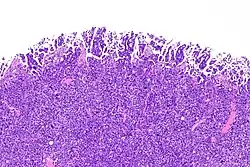

Rak urotelialny in situ

Jest to niebrodawkowata zmiana, w której stwierdza się nabłonek wykazujący cytologiczne cechy złośliwości[97][98]. Atypia może nie obejmować całej grubości nabłonka, zmiany mogą być obecne wyłącznie w warstwie podstawnej lub pokrywać nabłonek o prawidłowym wyglądzie[97]. Rak in situ często jest wieloogniskowy i może być rozproszony. Zmiany mogą występować synchronicznie lub pojawiać się metachronicznie[97].

Nowotwór zwykle pojawia się w piątej i szóstej dekadzie życia[97]. Makroskopowo rak in situ jest płaską zmianą, błona śluzowa może wykazywać zaczerwienienie lub obrzęk, jednak makroskopowo może pozostać niezmieniona[97][99]. Zmiany pojawiają się przede wszystkim w obrębie pęcherza moczowego, jednak u części chorych nowotwór jest obecny w zakresie końcowego odcinka moczowodów oraz prostacie[97].

W obrazie mikroskopowym występuje anaplazja jądrowa porównywalna z rakiem urotelialnym o wysokim stopniu złośliwości, jądra komórkowe są wyraźnie powiększone, hiperchromatyczne, chromatyna jest gruba, mogą być obecne duże jąderka[97][98]. Obserwuje się utratę polarności komórek z nieregularnym stłoczeniem jąder komórkowych. Cytoplazma jest eozynofilna lub amfofilna[97]. Mitozy są częste, mogą być obecne w każdej warstwie urotelium i sięgać górnych warstw urotelium[97][99].